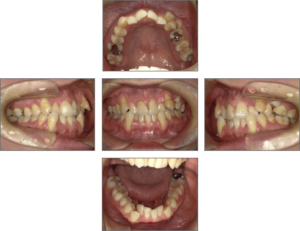

• 30_bf

30_bf

理事長 萬 建一 歯科医師

歯学博士 / 一般社団法人日本歯科専門医機構認定 矯正歯科専門医 / 日本矯正歯科学会 認定医 / 日本成人矯正歯科学会 認定医・臨床指導医・総合指導医

院長 平田 彩子 歯科医師

日本矯正歯科学会 認定医 / 日本成人矯正歯科学会 認定医